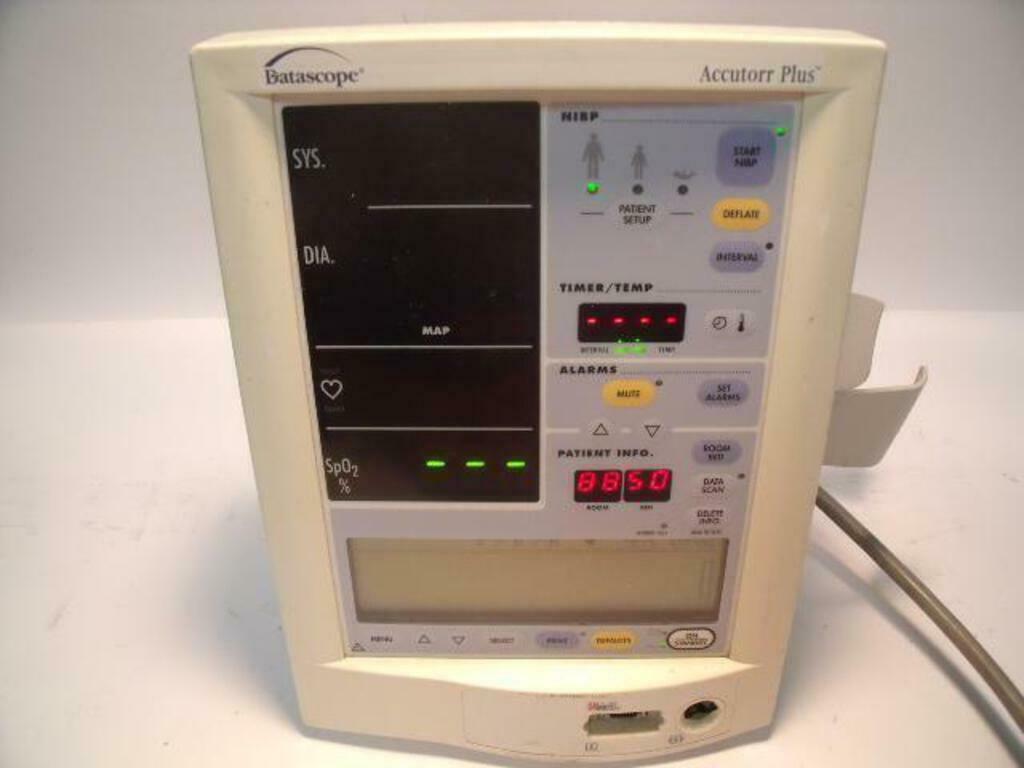

DataScope Accutorr Plus SN A7110378 K7 Vital Signs Monitor | PR3037

Sale price$ 163.18

Regular price$ 199.00